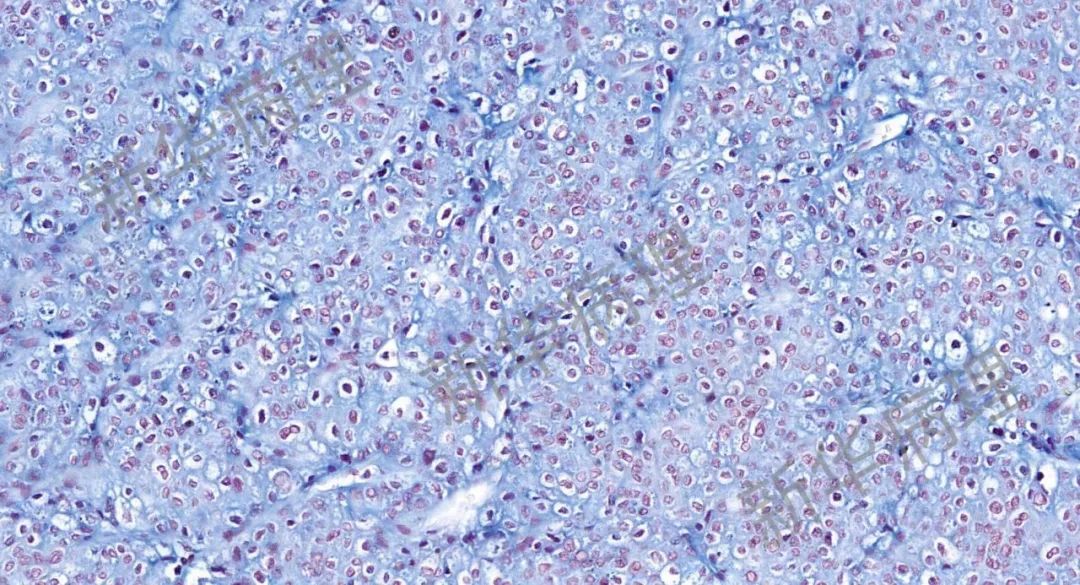

幽门螺杆菌(W-S染色)